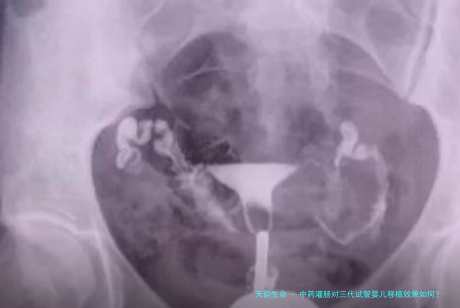

中药灌肠对三代试管婴儿移植效果怎样?

中药灌肠在提高三代试管婴儿胚胎移植的着床率方向,展现出其特殊的疗效。这类疗法不仅有助于盆腔液体的吸收与炎症的控制,还能有效促进肠道爬动,防止移植后肠道不适。更重要的是,它可以有效抑止子宫内炎症,降低盆腔局部炎症的发生,进而压低因炎症引发的异常子宫压缩,提高胚胎移植的成功率。

中药灌肠在治疗子宫腔体内炎症、改善子宫内膜厚薄程度方面具有卓越效果,从而在某种程度上提高胚胎的着床率。同时它还能推进胃肠功能,缓解因使用大量促泡激素和黄体酮导致的便秘。在移植前正在进行药灌肠治疗,有益于术后胃肠功能的恢复。